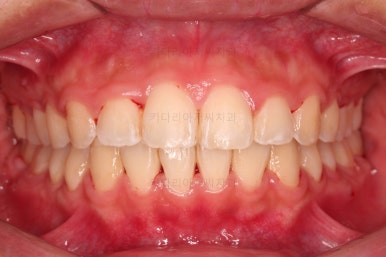

입매가 매우 좋아졌습니다.

과연 11개월의 치료결과가 맞나 싶을 정도로 깜짝 놀랄만큼 만족스러운 치료결과였는데요.

환자분은 모르겠지만, 특정 한 포인트만 개선되면 매우 좋아질 수 있다는 중요 포인트가 있었는데 그 부분이 완벽해졌습니다.

그래서 입이 실제로 발치교정만큼 많이 들어가지는 않았는데, 그 포인트 위주로 치료를 하니 결과물이 굉장히 좋아졌던거죠.(그 포인트가 뭔지는 영업비밀입니다😀)

마무리 후에 사진을 같이 보며, 환자분께는 농담 반 섞어서 상황때문에 어쩔 수 없이 비발치로 결정했지만, 오히려 발치를 안하길 잘했다는 생각이 든다라는 말씀까지 드릴 정도로 만족스러운 치료결과를 얻을 수 있었습니다.